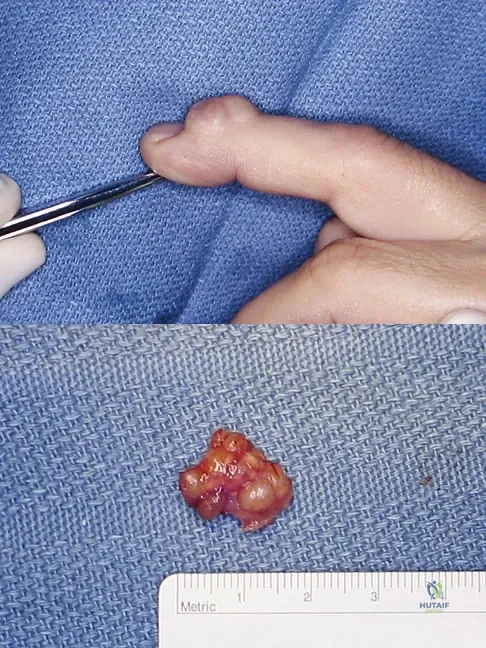

A 58-year-old woman has had a slowly progressing mass over the distal interphalangeal (DIP) joint of her dominant hand with a worsening deformity of her nail. She has no significant medical history but underwent bilateral knee arthroplasties 1 year ago. Radiographs reveal a small osteophyte at the DIP joint dorsally. A clinical photograph and a biopsy specimen are shown in Figures 76a and 76b. What is the most likely diagnosis?